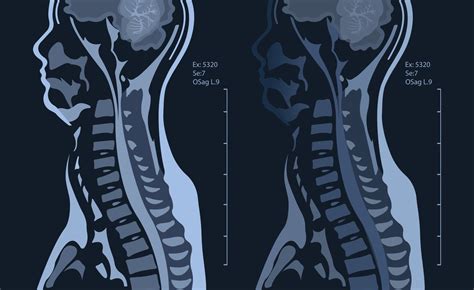

Spinal Disorders Evaluates the spine for herniated discs, spinal stenosis, and other conditions affecting the spinal cord and nerves.